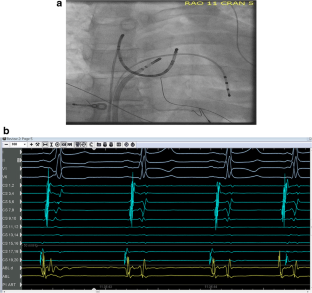

Fig. 1

Fig. 2

Fig. 3